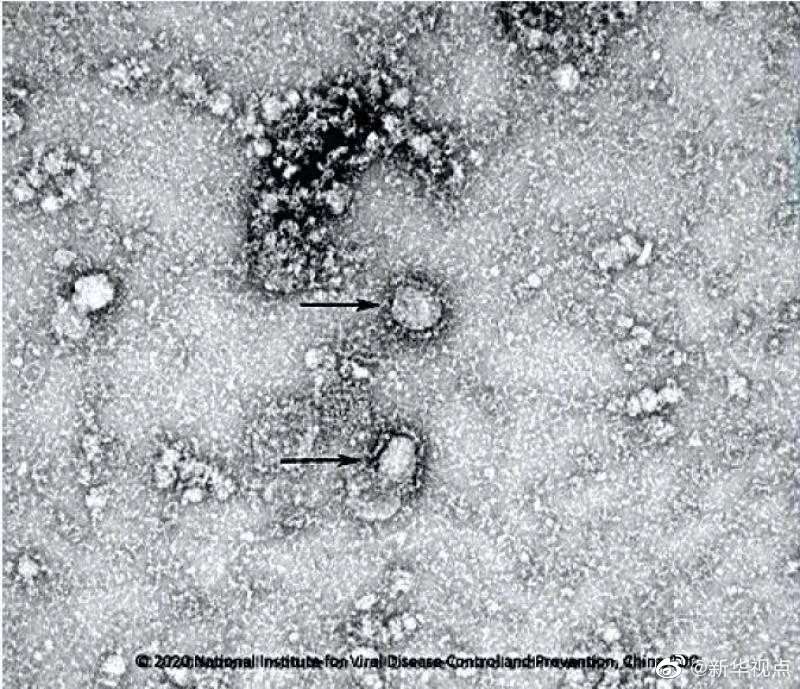

好消息!中国疾控中心成功分离我国首株新型冠状病毒毒种,它长这样!

国家病原微生物资源库于2020年1月24日发布了由中国疾病预防控制中心病毒病预防控制所成功分离的我国第一株病毒毒种信息及其电镜照片、新型冠状病毒核酸检测引物和探针序列等国内首次发布的重要权威信息,并提供共享服务。看病毒“真容”↓↓↓(记者 田晓航、王秉阳)